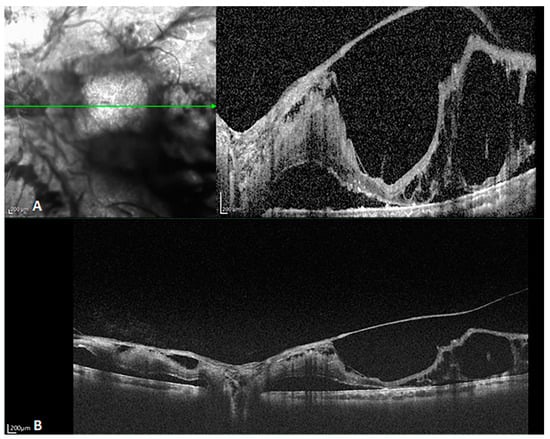

SD-OCT has a limited scope of examinations, and folding artifacts are an inescapable problem because of the technique’s limited imaging depth. When the width of the examined field is expanded, the OCT system requires a deeper range to surround the whole field and avoid folding artifacts. SS-OCT overcomes this problem by enhancing the detection resolution of the interference spectrum. Consequently, it has an impressive range and quality, as demonstrated in Figure 5.

Figure 5.

B-scan images of a patient with proliferative diabetic retinopathy. (A) SD-OCT showing retinal detachment, with the large proliferative membranes, causing a folding artifact. The choroidal layer is incompletely captured. SD-OCT was unable to capture the whole proliferating membrane and the choroidal tissue below because the retinal bulge was too high (The green arrow in the left image indicated the orientation of B scan OCT in the right image). (B) SS-OCT displays an almost identical position. It reveals details of the retina and choroid, even including the choroidal–scleral boundary and part of the sclera. The pre-retinal proliferating membrane extending into the vitreous cavity and the retinal detachment on the nasal side of the optic disk are also clearly visible.